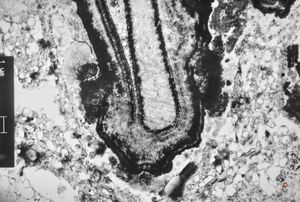

M,7y. | epidermolysis bullosa (dystrophic type) - oral mucosa